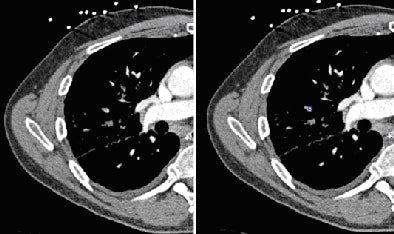

![]() |

| Segmental embolus indicated by blue square (right image) -- PE was missed by both inexperienced readers upon initial interpretation (left image) without CAD as a second reader. All images courtesy of Dr. Joseph Schoepf. |